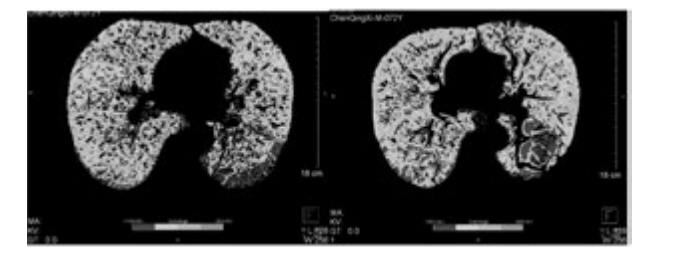

從表3、表4提示,CT 值在-1000 至-951 比例有所下降,Class4( % ) 亦明顯下降,故肺氣腫較治療前好轉。

下圖為雙源CT肺實質分析軟件,深藍色表示CT值在-1000 至-951,治療后較治療前深藍色面積明顯縮小。